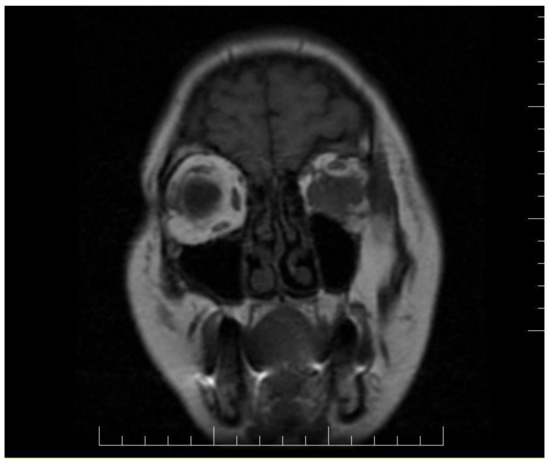

Ophthalmologic and neurologic examinations revealed reduced visual acuity, reduced mobility in all directions of the eye, normal intraocular pressure, hypoesthesia of the left hemi-face, paresis of the 3rd and 4th nerve of the left eye and paresis of the 5th nerve. Magnetic resonance imaging (MRI) and computed tomography (CT) scan detect a tumor situated in the left retroocular space in the intraconal area, which cuffs the left optic nerve and invades the extra-ocular muscles (Figure 1 and Figure 2). Differential diagnosis included diabetic retinopathy, thyroid ophthalmopathy, lymphoma, primary or metastatic neoplasia. The thyroid function tests were normal and the ophthalmologic exam excluded diabetic retinopathy.

Figure 1. Brain CT scan showing an inhomogeneous mass with contrast agent capture in the retroocular space of the left orbit, cuffing the left optic nerve.

Figure 2. Brain MRI exhibiting a left retroocular intraorbital tumor, which infiltrated the ocular muscles in three out of quarter quadrants.